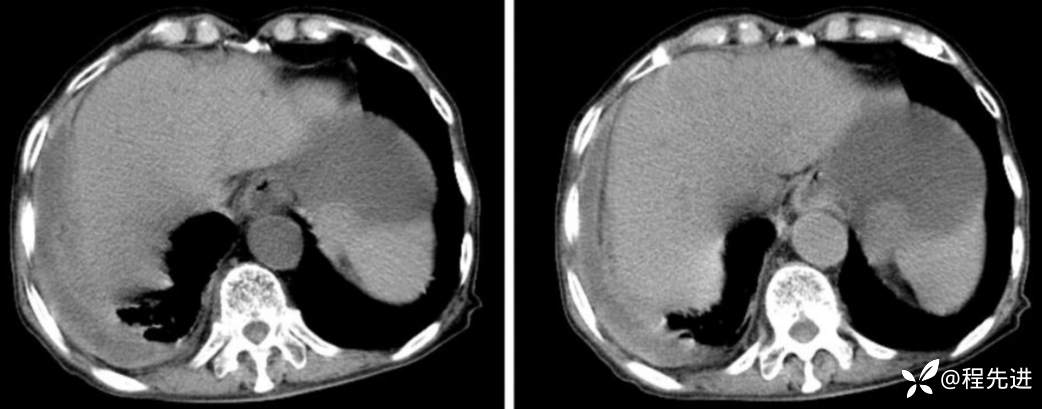

CT

平扫